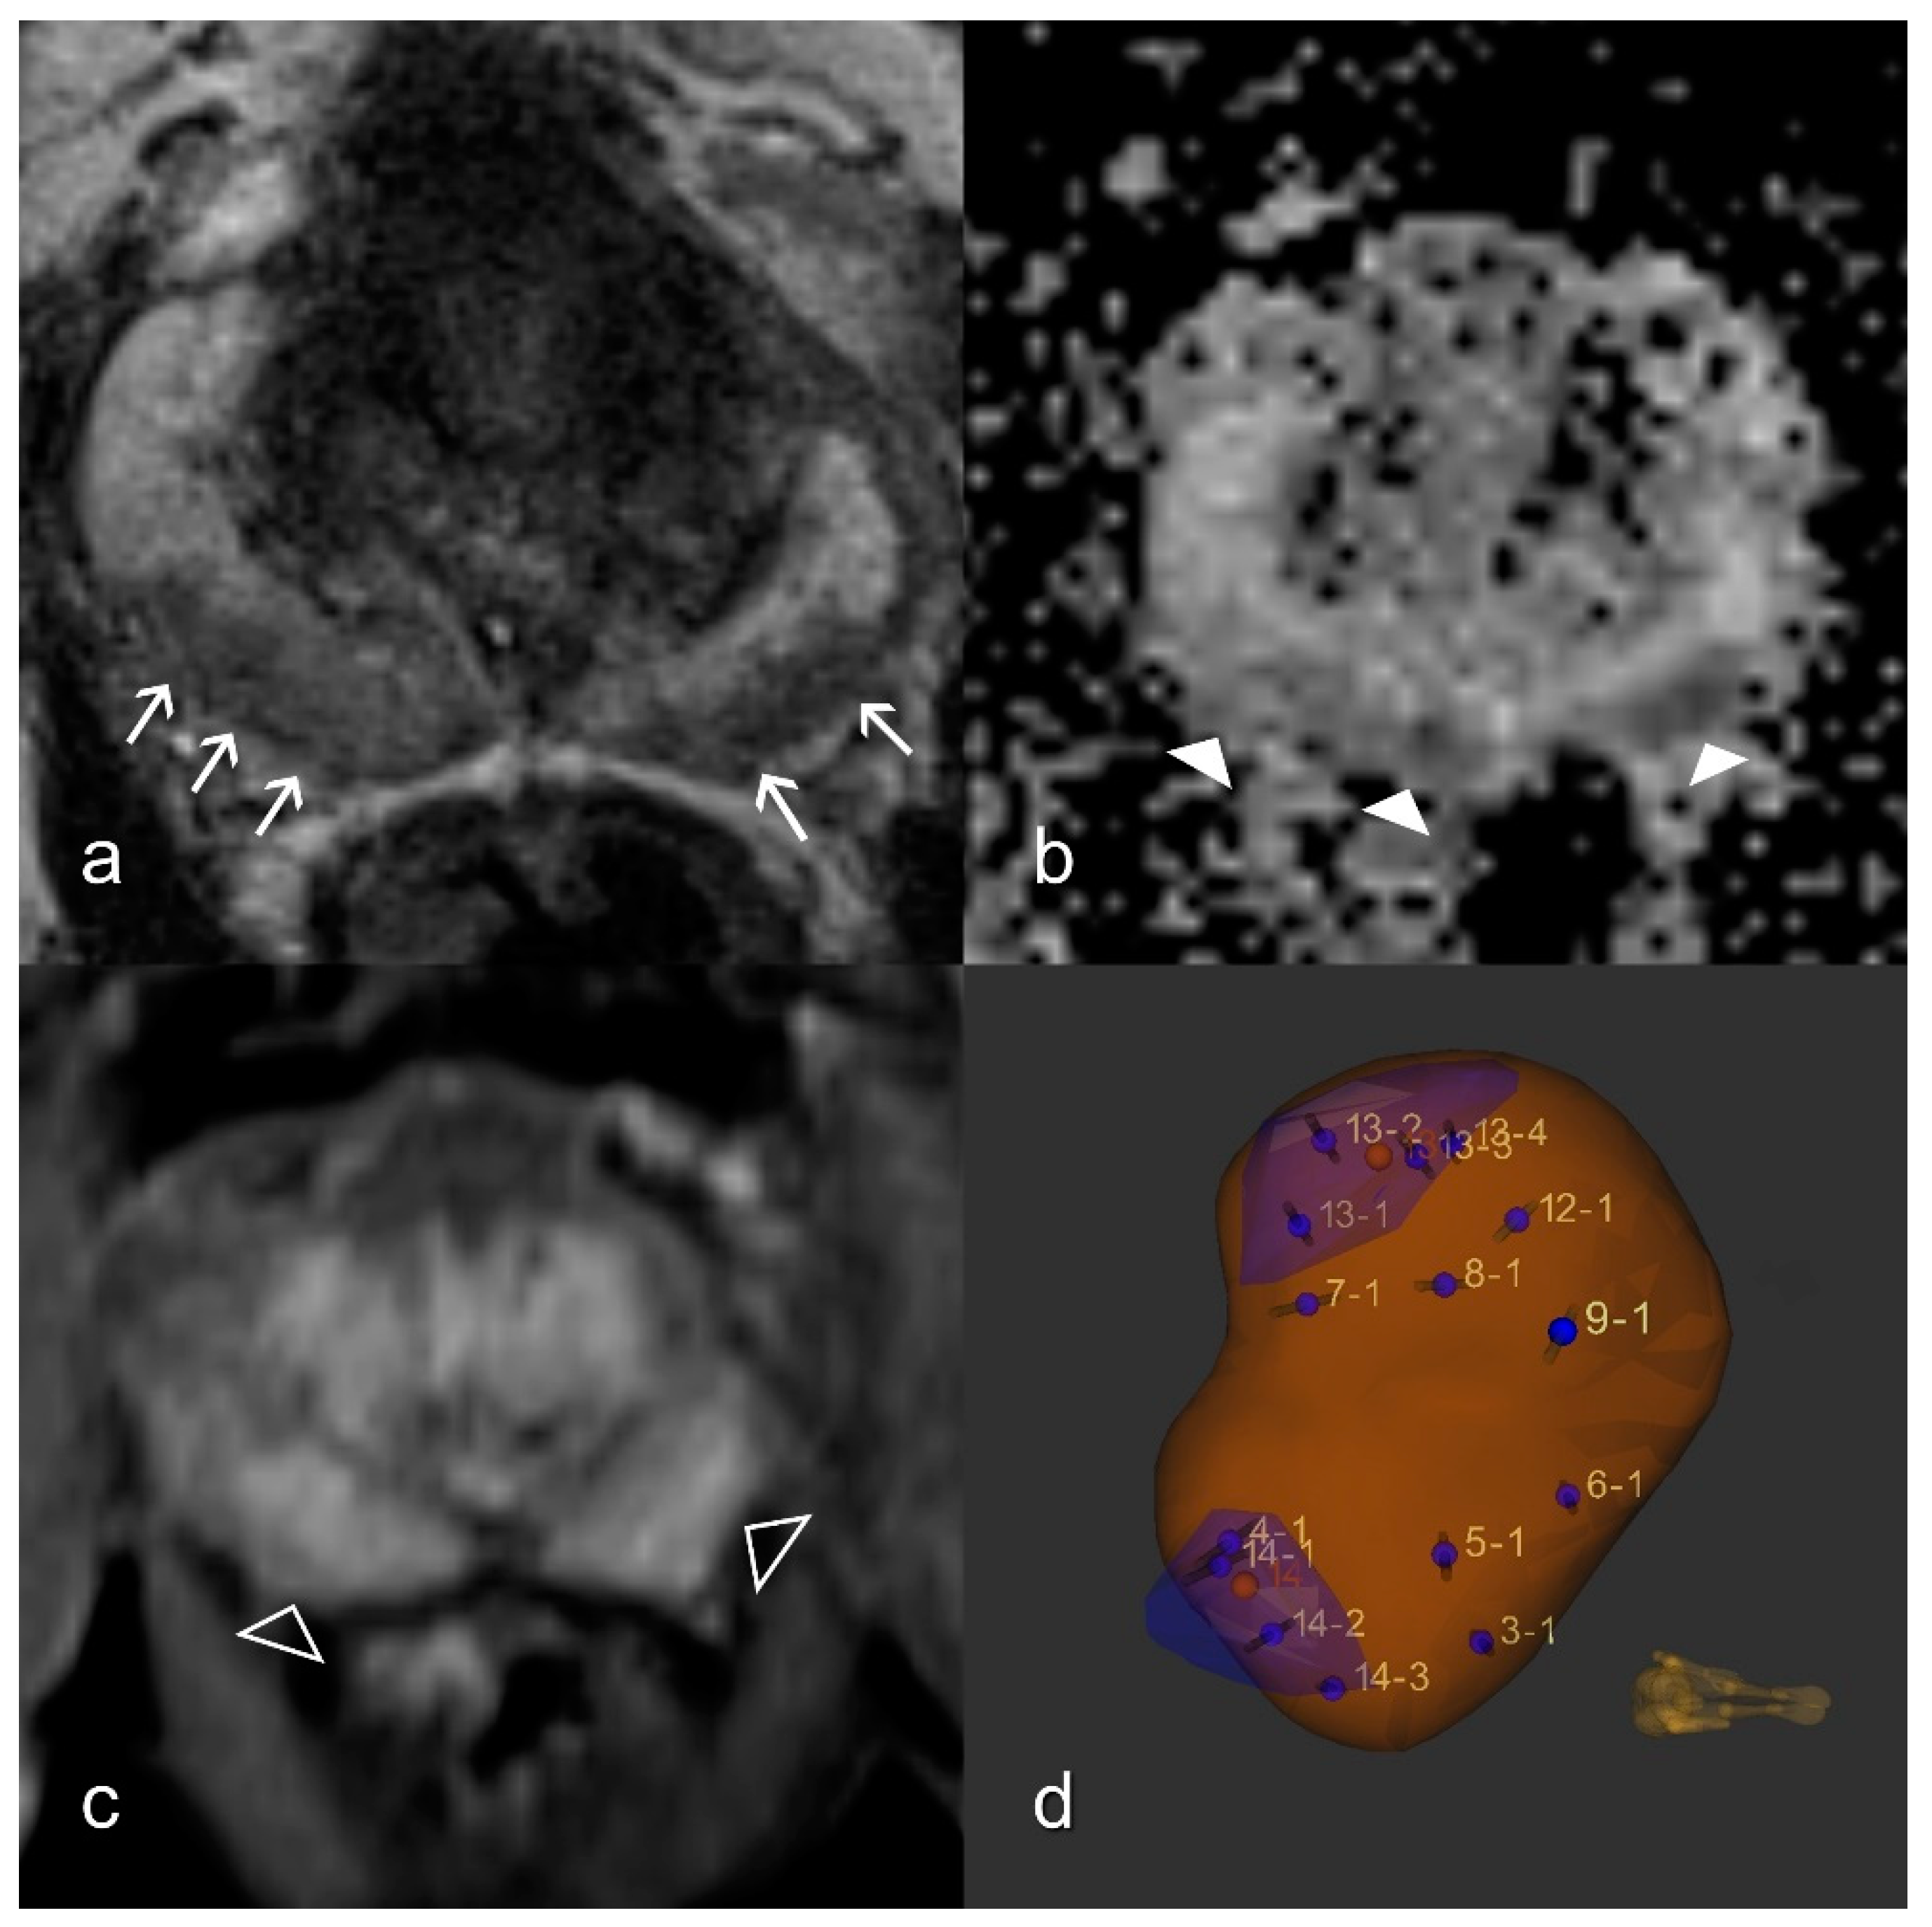

Figure 2.

Reference standard. Imaging findings showing patchy T2W signal attenuation (white arrows) in the peripheral zone on both sides (a), moderate reduction (white arrowheads) in the ADC map (b), and diffuse enhancement (empty arrowheads) in the dynamic T1W VIBE (c); Formally, this represents the PI-RADS 3 constellation; (d) The MRI/ultrasound (US)-guided biopsy 3D model depicts the target lesions in the blue zones and the template biopsy cores (numbered). Pathology confirmed no malignancy. ADC, apparent diffusion coefficient; T1W, T1-weighted; T2W, T2-weighted; VIBE, Volumetric interpolated breath-hold examination.